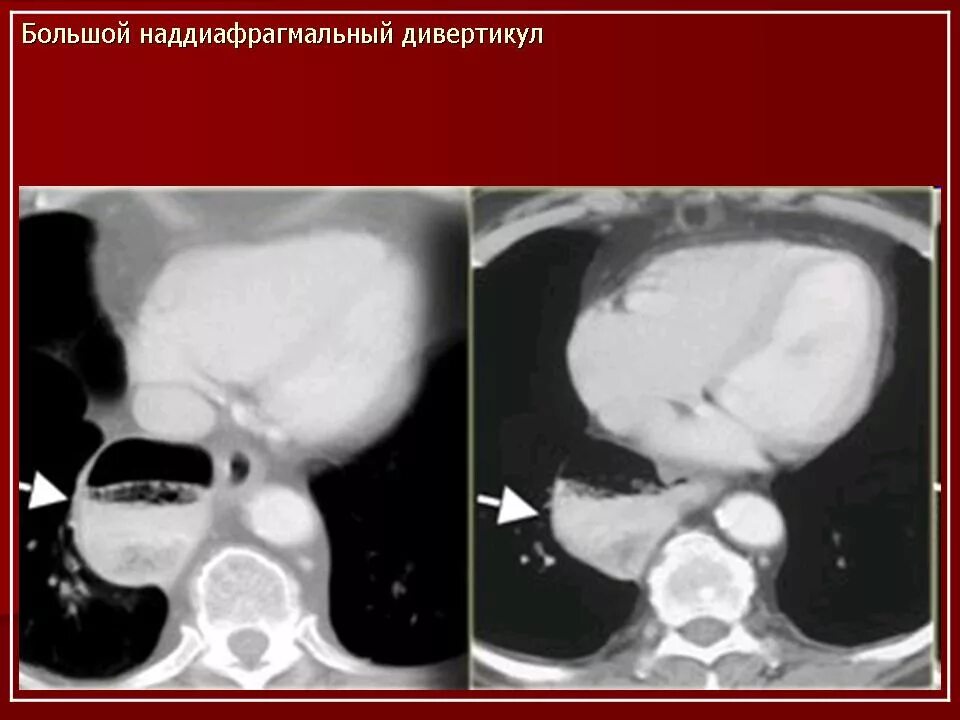

Дивертикул трахеи